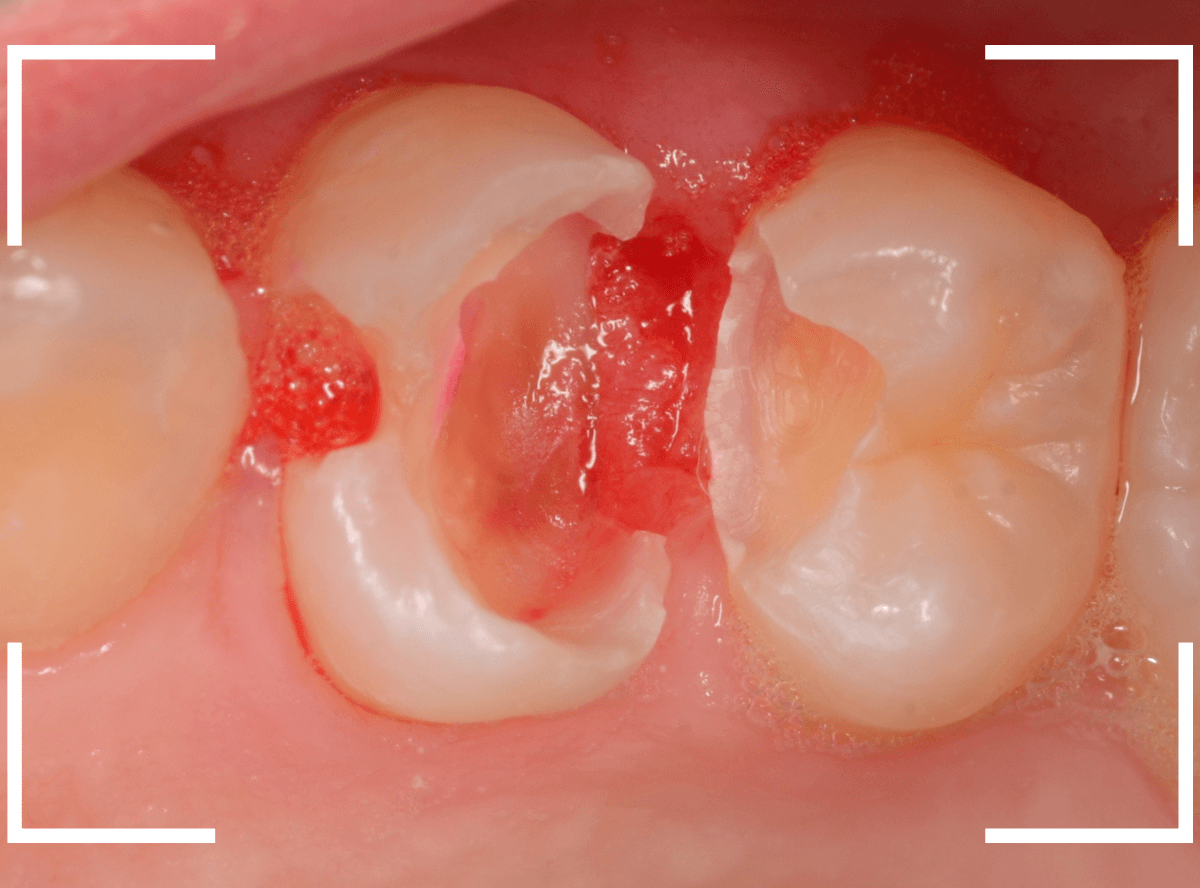

治療を開始します。

先ほどの黒く見えた部分は少し削るとすぐに虫歯が出てきました。

手前の歯まで虫歯を除去した時点で、う蝕検知液で確認します。

赤く染色されている部分が虫歯です。

思ったよりも深めの虫歯ですね。

レジンを除去して虫歯をすべて治療したところです。

レジンの中も全体にうっすらと虫歯になっていました。

このくらいの虫歯でも、患者さんは自覚症状はありませんでした。